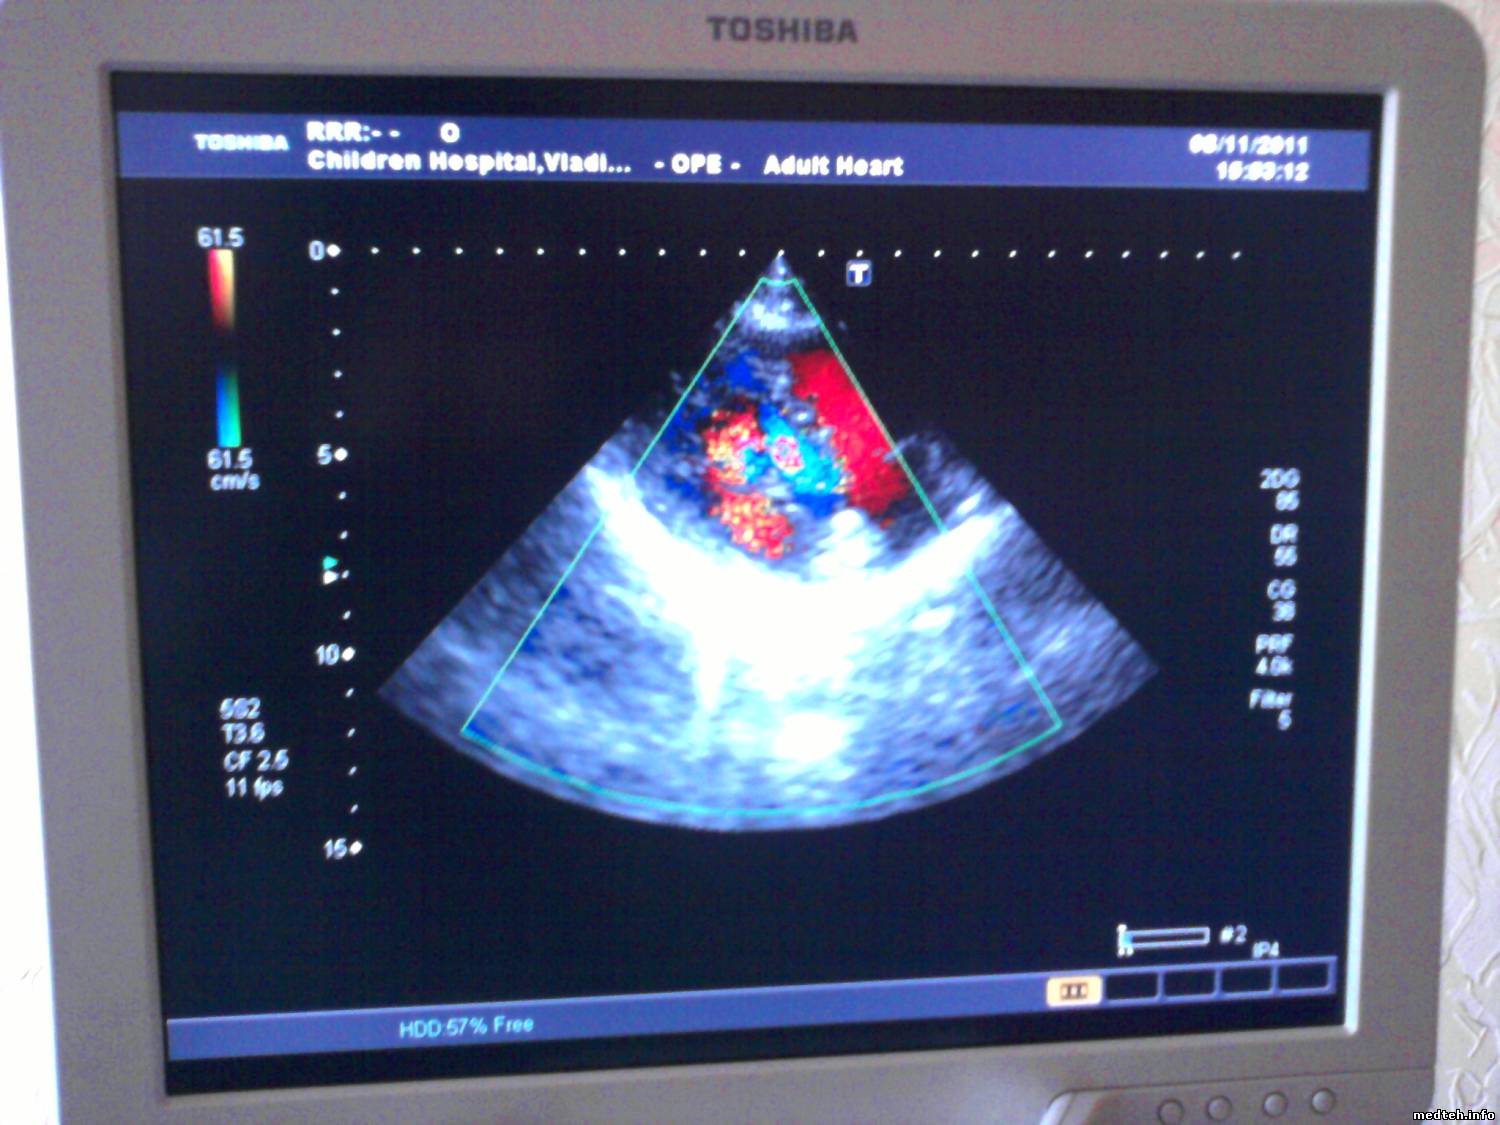

Ах, да. Фотку выкладываю. Как мне объяснили на изображении не должно быть красно-синей ряби. Со слов врача плохой сигнал в диапазоне 2МГц

0441141.jpg (237.8 Kb)

РОМУЛДата: Среда, 02.Ноя.2011, 20:16 | Сообщение # 56

Снимок совершенно не показательный. Датчик детский кардиологический, пресет выбран "взрослая кардиология", а на изображении вроде как почка. Частота кадров низкая, скоростные показатели цветного допплера установлены скорее для периферических сосудов. У Вас там чего, совсем "нулевые" доктора? ireful